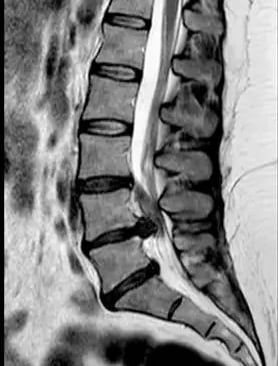

La hernia lumbar puede irritar una raíz nerviosa y provocar:

- Dolor lumbar (zona baja de la espalda)

- Ciática: dolor que baja por glúteo, muslo o pierna

- Hormigueo o adormecimiento en pierna o pie

- Calambres o sensación de corriente

- Pérdida de fuerza (pierna que “falla”, dificultad para caminar de puntillas o talones)

- Dolor al sentarte, conducir, agacharte o mantener posturas durante tiempo

Hernia discal lumbar: síntomas más frecuentes